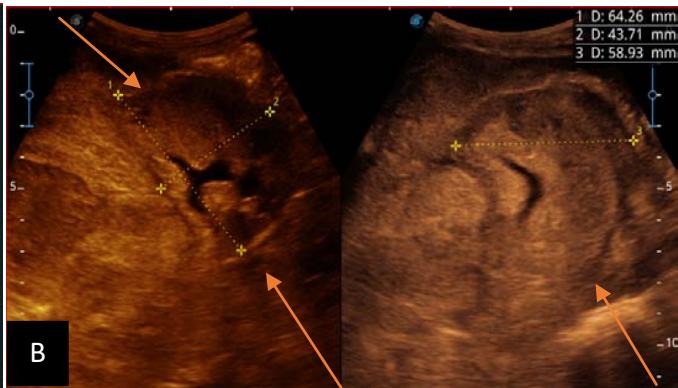

Figure 6: 9-year-old sickle cell patient, referred for abdominal bloating with significant collateral venous circulation, in whom we noted: Image A: mass, Image B: healthy renal stump, inferior polar; Image C: left transmedian extension, Image D: thrombosis of the vena cava segments: supra, retro and sub hepatic, sparing a part of the supra hepatic vena cava segment over $30~\mathrm{mm}$. Image: Ascites of great abundance, Image F: normal left kidney, Image G: splenic microcalcifications, Image H: celiac adenopathy, Image I: sub pleural pulmonary nodules with the biggest measuring $3.88 \times 3.81 \mathrm{~mm}$, Image j: left pleurisy of great abundance. Source: Dr. Frederick Tshibasu Tshienda database.